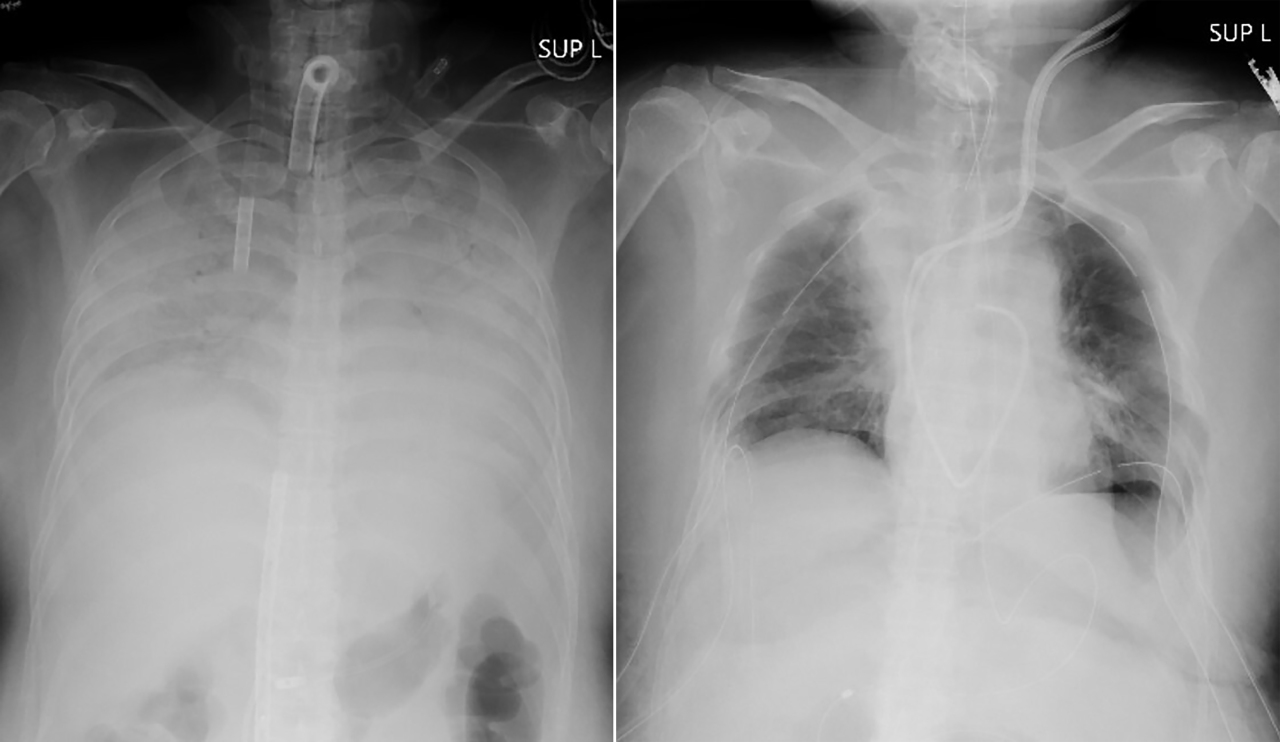

This combination of radiographs provided on April 9, 2021, by Kyoto University Hospital, shows the chest of a patient before the surgery, left, and after the surgery, right. Doctors in Kyoto University Hospital announced Thursday, April 8, 2021, they have successfully performed the world’s first transplant of lung tissue from living donors to a patient with severe lung damage from COVID-19. (Kyoto University Hospital via AP)